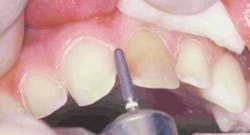

Preparation of the four incisors was then initiated using diamond burs from the Shofu Contemporary Cutting Kit (Figure 5). With the high-speed ElectroTorque KaVo handpiece, a small round diamond (0872-1) was used to outline the peripheral margins of the preparations (Figure 6). By scoring the facial surface of the incisors with the depth cutter (0897-1) (Figure 7), smooth and uniform tooth structure removal using a coarse tapered diamond (0835C-1) was facilitated (Figure 8). As tooth nos. 9 and 10 were prepared, it came time to address the gingival contour issues of the inflamed interproximal gingiva.